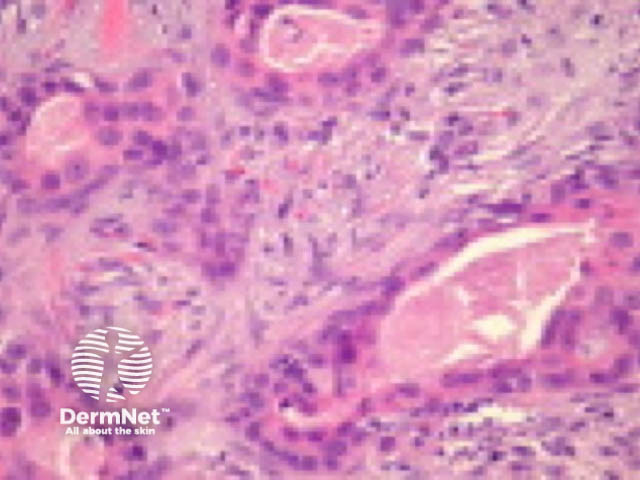

Typically SCC is graded as:

Grading of SCC depends on how easy it is to recognise the characteristics of squamous epithelium (eg. intracellular bridges, keratinisation), pleomorphism and mitotic activity. There is considerable inter-observer variation in grading SCC.

Figure 4